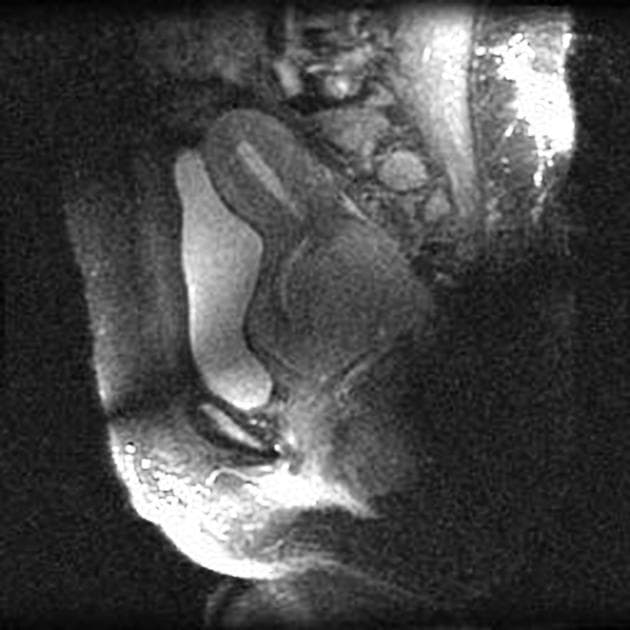

Axial T2

MRI•Axial T2•1 / 24

- Khối ung thư cổ tử cung kích thước lớn, lan tỏa tại chỗ, kích thước 22 x 40 x 42 mm, xuất phát từ thành sau bên trái của cổ tử cung và lan xuống phía dưới vào phần một phần ba trên của âm đạo ở vùng giữa đến sau bên trái.

- Khối cũng xâm lấn parametrium ở vùng trước bên trái.

- Ghi nhận bệnh lý hạch (lymphadenopathy) có tín hiệu bất thường, đường kính trục ngắn tối đa (SAD) 8 mm, nằm ngay dưới vị trí phân nhánh của tĩnh mạch chậu trong trái. Hạch này biểu hiện hạn chế khuếch tán (restricted diffusion) trên hình ảnh khuếch tán (DWI) và có tăng quang sau tiêm thuốc cản quang (post-contrast enhancement).

Các hình ảnh học cho thấy ung thư cổ tử cung giai đoạn IIIC1 theo hệ thống phân giai đoạn FIGO.

Trường hợp này biểu hiện ung thư cổ tử cung lan rộng tại chỗ với bằng chứng rõ ràng về xâm lấn parametrium và hạch chậu di căn, đáp ứng tiêu chuẩn giai đoạn IIIC1 theo hệ thống FIGO. Hạch vùng chậu trái có hạn chế khuếch tán và tăng quang sau tiêm thuốc, hỗ trợ chẩn đoán ác tính. Kết quả giải phẫu bệnh xác nhận ung thư biểu mô tế bào vảy kiểu sản sừng, dạng tổ chức học phổ biến nhất của ung thư cổ tử cung. Các tổn thương gan và thận lần lượt phù hợp với u mạch gan và nang vỏ thận đơn giản – đều là tổn thương lành tính, nhấn mạnh tầm quan trọng của việc định tính tổn thương chính xác để tránh phân giai đoạn quá mức. Việc phân giai đoạn chính xác định hướng điều trị, với giai đoạn IIIC1 thường được điều trị bằng hóa xạ trị thay vì phẫu thuật.